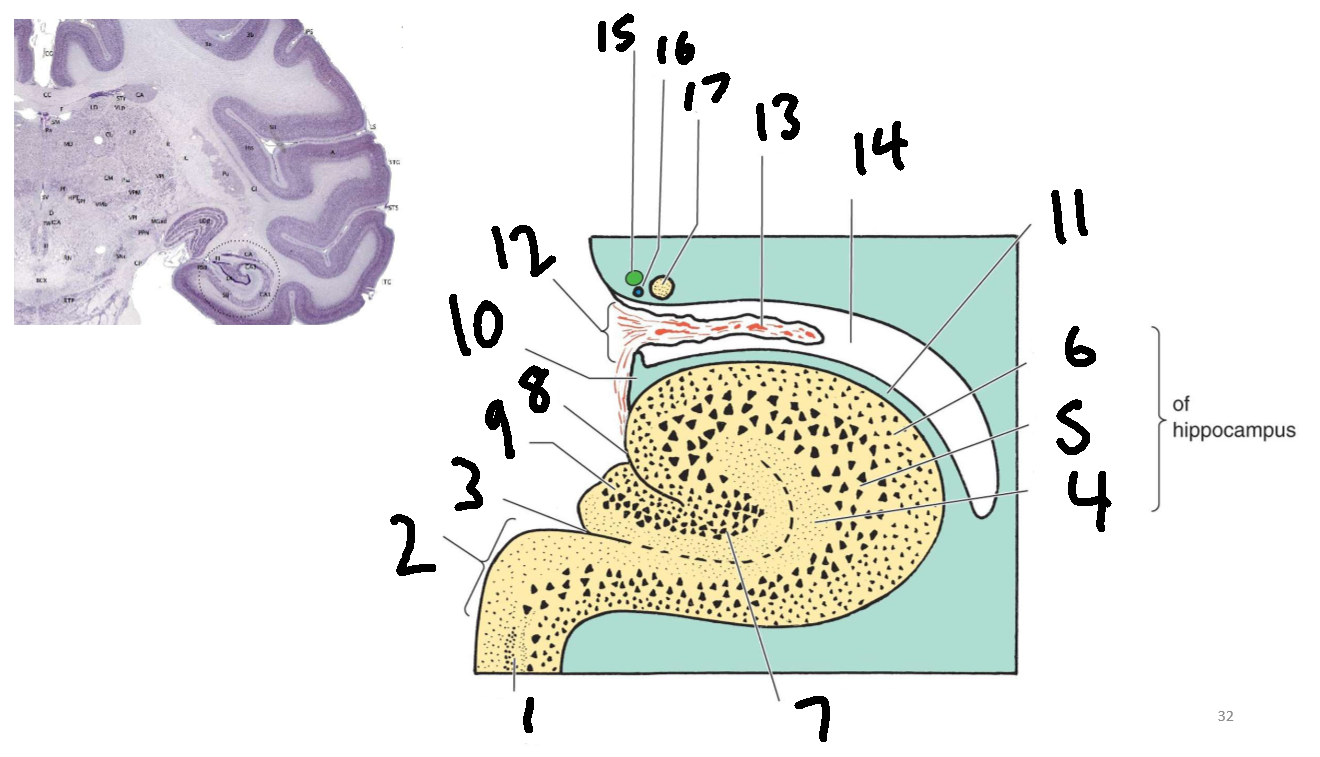

What is 1?

parahippocampal gyrus

What is 2?

subiculum

What is 3?

hippocampal sulcus

What is 4?

molecular layer

What is 5?

pyramidal layer

What is 6?

polymorphic cell layer

What is 7?

granule cell layer of dentate gyrus

What is 8?

fimbriodentate sulcus

What is 9?

dentate gyrus

What is 10?

fimbria of hippocampus

What is 11?

alveus

What is 12?

choroid fissure

What is 13?

choroid plexus

What is 14?

temporal horn of lateral ventricle

What is 15?

stria terminalis

What is 16?

thalamostriate vein

What is 17?

tail of caudate nucleus